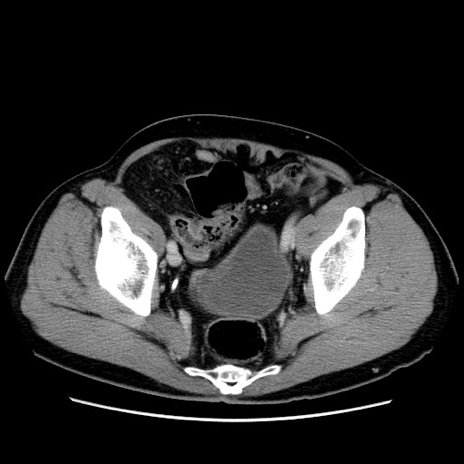

症例34(横断像)

【症例】60歳代 男性

【主訴】右鼠径部膨隆

【現病歴】1年程前より右鼠径部膨隆あり。自己にて還納可能だったため放置していた。3時間前より右鼠径部の脱出を認め、還納困難となり受診。

【身体所見】右鼠径部に小児頭大の膨隆あり。弾性硬であり、用手還納は困難。左鼠径部にも膨隆を認める。脱出はなし。